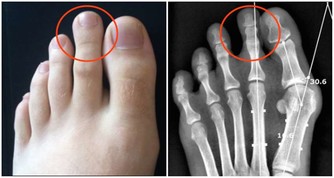

痛風石中老年人比較常見的疾病之一,男性患者比較多,往往夜間突然發病,局部關節紅腫、疼痛劇烈,皮膚會呈青紫色、發亮,有明顯的壓痛感以及局部隆起現象,有時關節還會有活動障礙現象的發生。